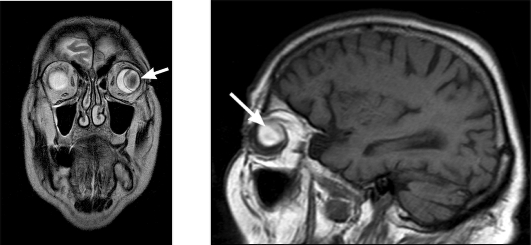

МРТ: возможна визуализация рентгенонеконтрастных

инородных тел (см. рис. 8).

Рис. 8. МР-томограмма. Пластмассовое инородное

тело левого глазного яблока (стрелка)